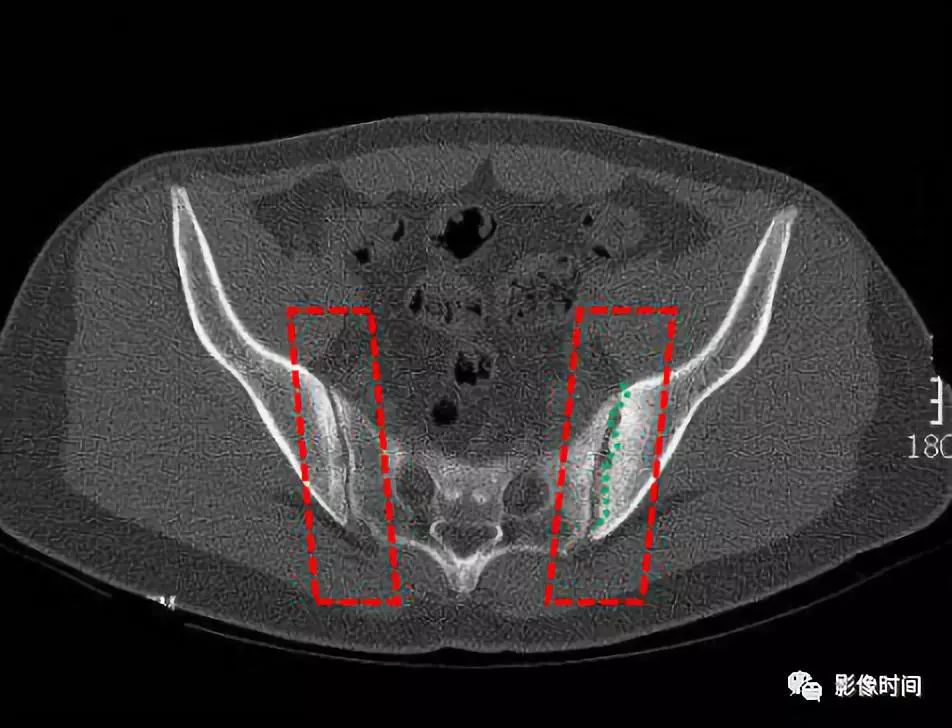

早期现为骶髂关节炎,病变一般在骶髂关节的中下部开始,为两侧性。可见斑点状或块状,髂骨侧明显。 医学百科网 | YxBaike.Com

继而可侵犯整个关节,边缘呈锯齿状,软骨下有骨硬化,骨质增生,关节间隙变窄,最后关节间隙消失,发生骨性强直。

医学百科网 | YxBaike.Com 双侧骶髂关节可见斑片状密度增高影,边缘欠规则,左侧骶髂关节呈锯齿状改变,关节间隙变窄。 医学百科网 | YxBaike.Com